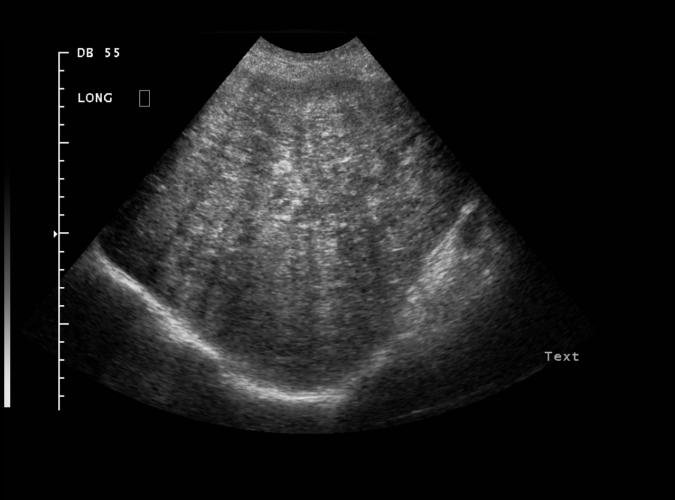

av Catherine Olsson, sonograf

Patologi.

Höger leverlob. Diffus levermetastasering från bröstcancer.

Catherine Olsson, sonograf